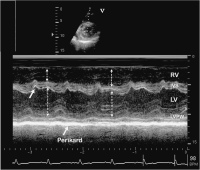

Abbildung 3: M-Mode des linken Ventrikels bei einem Patienten mit PC. Das Perikard ist mit 5 mm deutlich verdickt. Charakteristisch sind die abnorme Septumbewegung (Pfeil), die diastolische Abplattung der Hinterwand und die respiratorischen Schwankungen der Durchmesser des linken und rechten Ventrikels (unterbrochene Pfeile).